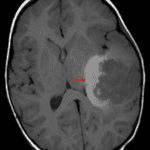

Age: 3

Sex: Male

Indication: Speaking difficulty, imbalance

Atypical teratoid/rhabdoid tumor (AT/RT)